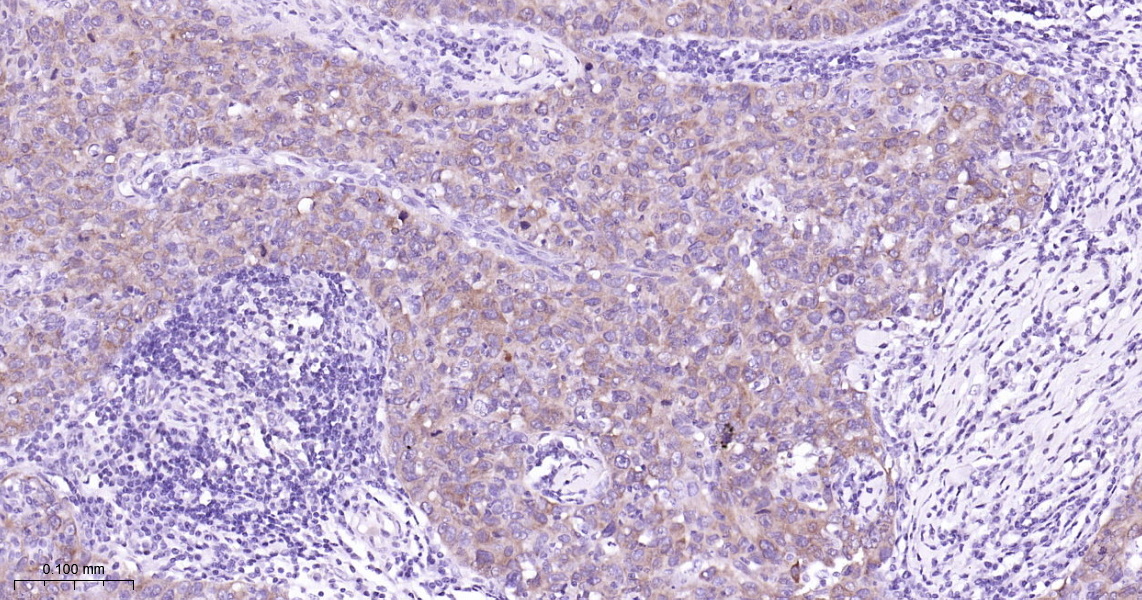

• IHC-P

IHC-P IHC-P1:50-200